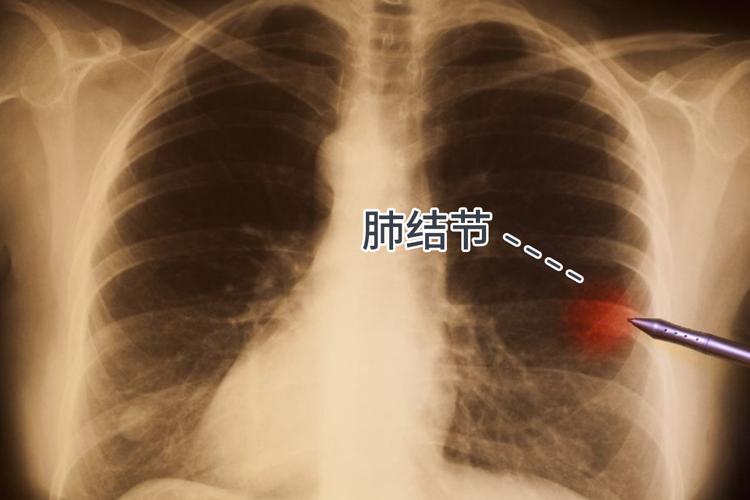

很多人對肺結節其實都有誤解,肺結節它是影像學上的一個術語,只要肺部出現類似結節的形態,都會用結節來稱呼它,它並不是疾病的名稱

很多原因都可能導致肺結節的形成,包括真菌、寄生蟲、結核、膿腫等感染性因素,以及類風溼性關節炎、血管炎等等非感染性因素。

人們健康意識逐漸增強,隨着體檢以及胸部低劑量CT 的普及,肺結節的檢出率逐年升高,據統計肺結節的發病率35.5%,也就是說每5個人中就有1個人身上有肺結節的可能,但是大家不要談“結”色變。很多人在體檢中發現肺結節後,都十分焦慮緊張,不知道自己的結節能不能自行消失。